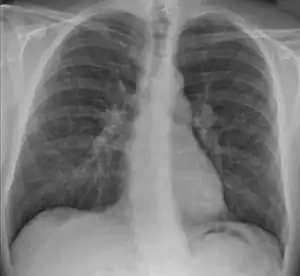

Chest X-ray showing the typical nodularity of sarcoidosis, predominantly in the hila of the lungs.

Chest radiograph changes are divided into four stages:[105]

1. bihilar lymphadenopathy

2. bihilar lymphadenopathy and reticulonodular infiltrates

3. bilateral pulmonary infiltrates

4. fibrocystic sarcoidosis typically with upward hilar retraction, cystic and bullous changes

Although people with stage 1 radiographs tend to have the acute or subacute, reversible form of the disease, those with stages 2 and 3 often have the chronic, progressive disease; these patterns do not represent consecutive "stages" of sarcoidosis. Thus, except for epidemiologic purposes, this categorization is mostly of historic interest.[28]